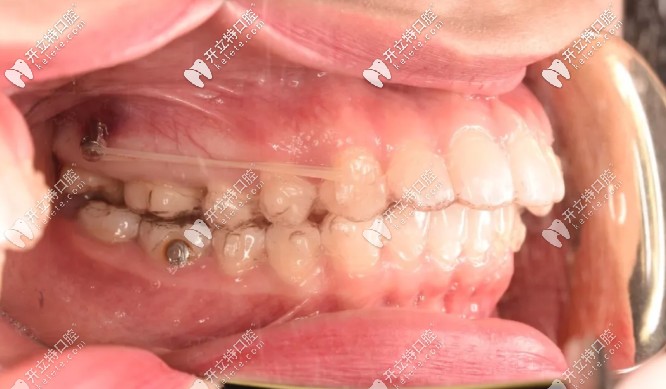

為了不拔牙,在設(shè)計(jì)方面時(shí)就溝通了打骨釘,我是在第18副的時(shí)候打的骨釘,看圖▼

術(shù)前把準(zhǔn)備好的布洛芬吃了,然后消毒打麻藥,到家后麻藥退了就是酸痛,異物感很重,頭兩天吃飯?zhí)赝纯?,還得注意清潔骨釘周圍,以防食物卡住。

完全恢復(fù)好之后,一點(diǎn)異物感都沒(méi)了!也米有不舒服的地方,就是得注意清潔,會(huì)有食物掛在骨釘那~